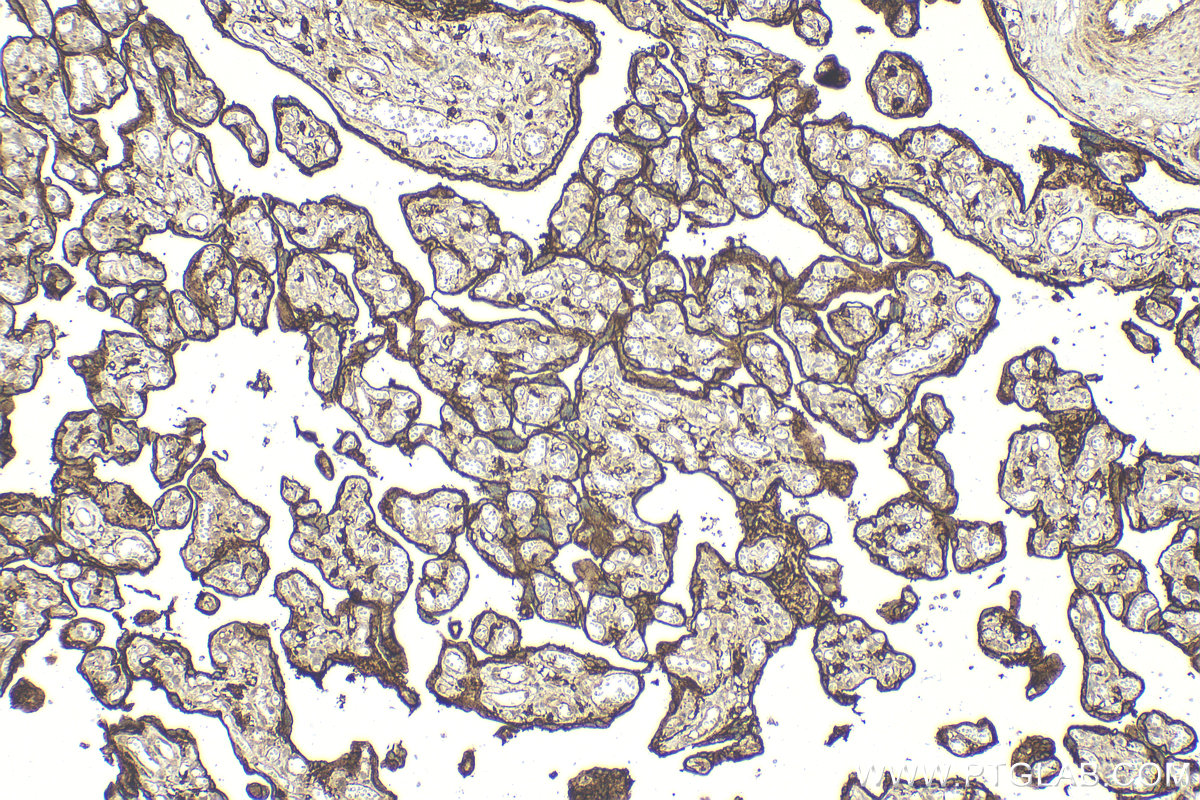

| Positive IHC detected in | human placenta tissue Note: suggested antigen retrieval with TE buffer pH 9.0; (*) Alternatively, antigen retrieval may be performed with citrate buffer pH 6.0 |

| Immunohistochemistry (IHC) | IHC : 1:200-1:800 |

15193-1-AP targets CD98/SLC3A2 in WB, IHC, IF/ICC, IP, CoIP, ELISA applications and shows reactivity with human samples.

CD98 is a cell-surface heterodimer consisting of a heavy chain (CD98hc) and a light chain. CD98hc also interacts with certain integrin b-subunits to regulate cell migration, survival, proliferation, and adhesion/polarity. CD98hc is overexpressed on the cell surface of many cancers and increased CD98hc expression is associated with the development and progression of tumors.(PMID:25084765). This protein has 4 isoforms with the molecular mass of 58-71 kDa and can be detected 85-94 kDa due to glycosylation. The glycosylated CD98hc can links to a non-glycosylated light chain (~40 kDa) via a disulfide bond to form a heterodimeric CD98 antigen with molecular mass of 120-130 kDa (PMID: 14770309).